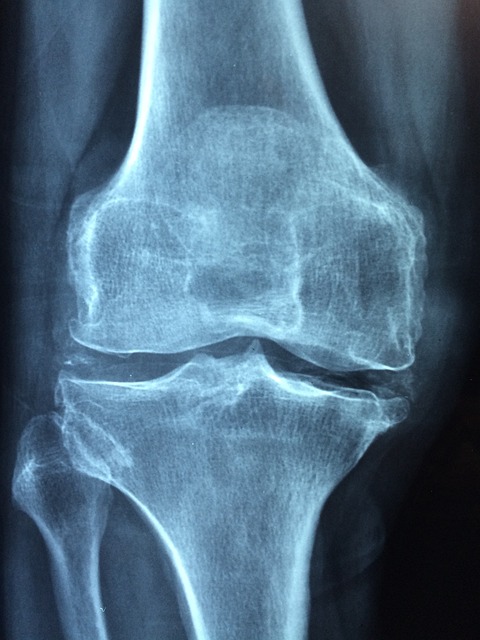

- X-레이: 슬개골과 대퇴골 사이의 정렬 상태를 평가하고, 뼈의 구조적 문제가 있는지 확인합니다. 그러나 X-레이는 연골 자체는 보여주지 않습니다.

- 관절염 발전: 연골연화증은 골관절염을 비롯한 다른 유형의 관절염으로 발전할 위험이 있습니다. 연골의 지속적인 마모와 염증은 관절의 영구적인 손상을 초래할 수 있습니다.